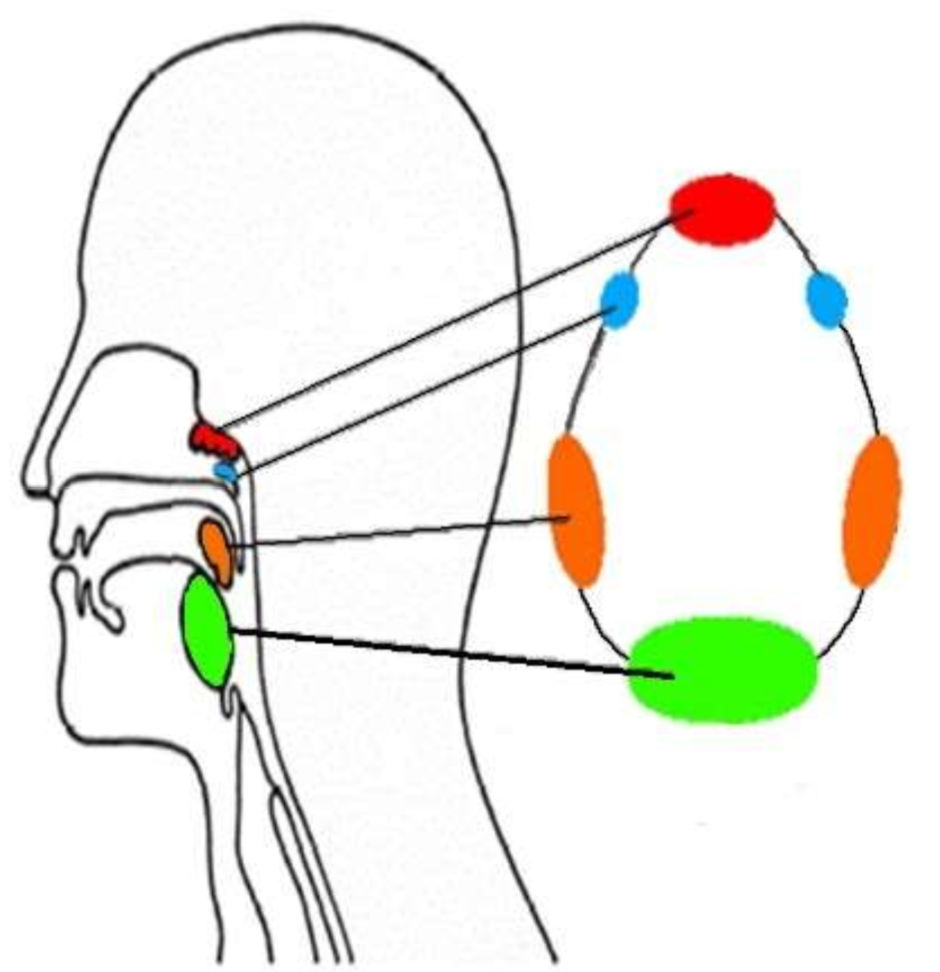

What is this group of structures called?

waldeyers ring

What is in red?

pharyngeal tonsil

What is in blue?

tubal tonsils

What is in orange?

palatine tonsils

What is in green?

lingual tonsil